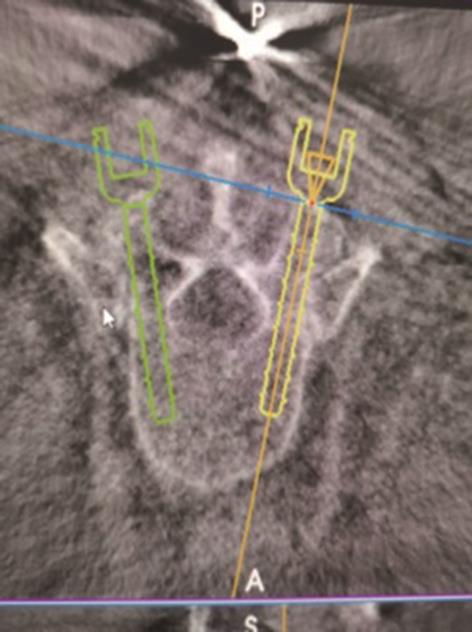

• 3种骶2髂骨螺钉置钉技术准确性的比较研究

2023, 48(11):1381-1386. DOI: 10.13406/j.cnki.cyxb.003371

摘要 (66) HTML (38) PDF 1.13 M (179) 评论 (0) 收藏

摘要:目的 比较传统徒手置钉,3D打印模板引导技术(three-dimensional printed template guided technique,TGT)和ball tip置钉技术在置入骶2髂骨(s2 alar-iliac,S2AI)螺钉的准确性。方法 回顾分析接受S2AI螺钉放置的145例患者,按置钉技术不同将其分为徒手技术组(36例)、TGT技术组(48例)和ball tip技术组(61例)。所有患者术前行骨盆CT确认最佳S2AI螺钉的最佳轨道参数,术后CT扫描评估螺钉轨迹的准确性,比较3种技术的置钉准确性。结果 3组患者S2AI螺钉的最佳轨道参数差异均无统计学意义(P>0.05);3组患者共置入S2AI螺钉290枚。其中,传统徒手技术组72枚,TGT技术组96枚,ball tip技术组122枚。传统徒手组置钉不准确率为18.1%(13/72),TGT技术组置钉不准确率3.1%(3/96),ball tip组置钉不准确率为4.1%(5/122):TGT技术组置钉准确性高于传统徒手技术组,差异有统计学意义(P<0.05);ball tip技术组置钉准确性也高于传统徒手技术组,差异有统计学意义(P<0.05);TGT技术组置钉准确性虽高于ball tip技术组,但差异无统计学意义(P>0.05)。结论 TGT技术和ball tip技术均为S2AI螺钉置入的可靠技术,二者的准确性均明显高于徒手技术,但ball tip技术操作简单。